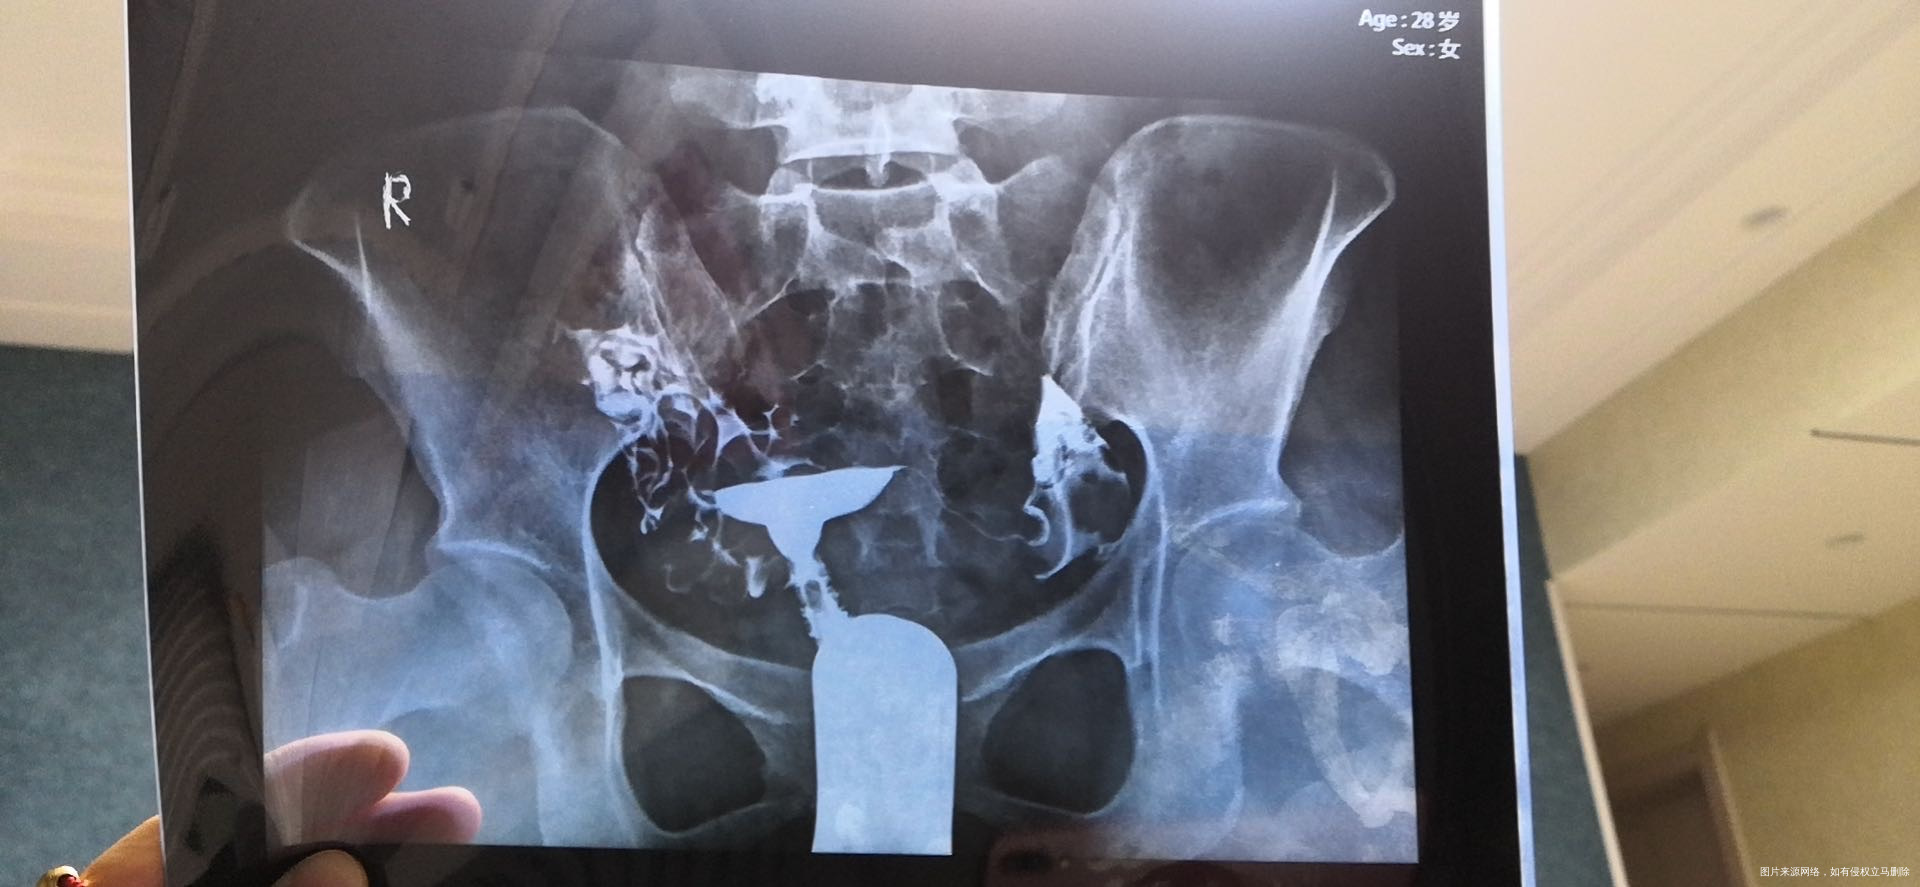

你好,你的输卵管伞端上举明显,在上面就会出现拾卵障碍,可以做腹腔镜处理输卵管,也可以直接做试管,具体的要看你的年龄、卵巢功能